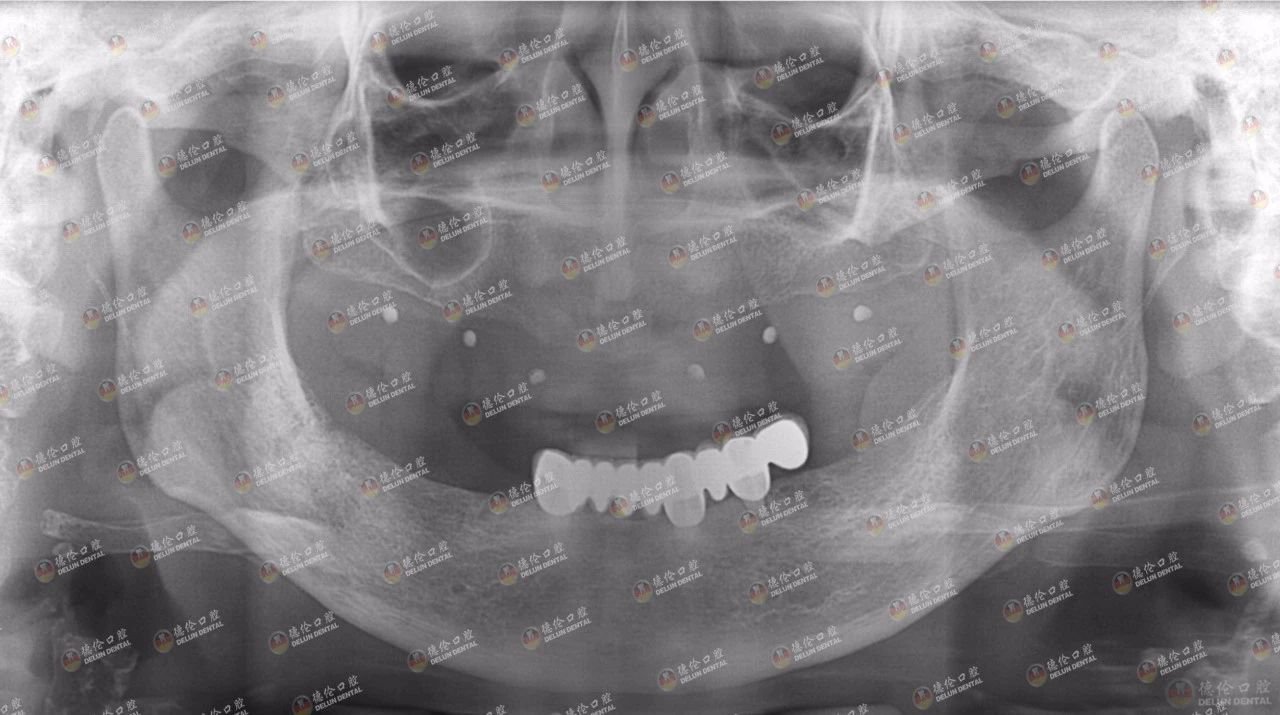

吴女士来德伦口腔诊疗时的牙片显示,只剩左下颌的种植牙,骨量不足